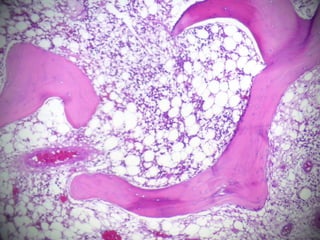

 COLON DERECHO QUE MIDE 20 CM DE

LONG, EL ILEON TERMINAL MIDE 10 CM Y

EL APÉNDICE CECAL 9 CM DE LONG. SE

OBSERVA DILATACIÓN A NIVEL DE LA

VÁLVULA ILEOCECAL DE 10 X 8 CM. AL

CORTE LA PARED ESTÁ ENGROSADA Y

MIDE 1 CM DE ESPESOR, LOS PLIEGUES DE

LA MUCOSA ESTÁN BORRADOS.

 LA RESECCIÓN SEGMENTARIA DE ILEON

MIDE 68 CM DE LONG. LA SEROSA

MUESTRA LESIONES BLANCAS

MILIMÉTRICAS Y A 0.6 CM DEL LÍMITE

QUIRÚRGICO SE IDENTIFICA UNA

CONSTRICCIÓN DE LA LUZ. LOS LÍMITES

QUIRÚRGICOS ESTÁN LIBRES DE LESIÓN

( A 6 CM ) EL EPIPLÓN MIDE 20 CM Y

PRESENTA UN NÓDULO DE 2 CM DE

DIÁMETRO.

 TUBERCULOSIS INTESTINAL Y PERITONEAL